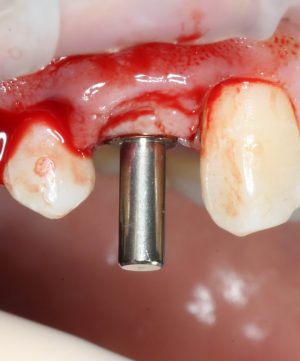

Установка формирователя десны.

Одномоментная установка формирователя десны позволяет сократить время и удешевить лечение — ведь по мере интеграции имплантата мы получаем нормально сформированный контур десны, готовый к установке протетической конструкции. Но это возможно лишь тогда, когда с объемами мягких тканей в области имплантата всё в порядке. То есть, как раз в нашем случае.

В CLINIC IN используют только одноразовые формирователи и только один раз:

С учётом клинических условий, мы подобрали к установленному имплантату формирователь Slim (без расширений) высотой 3 мм: